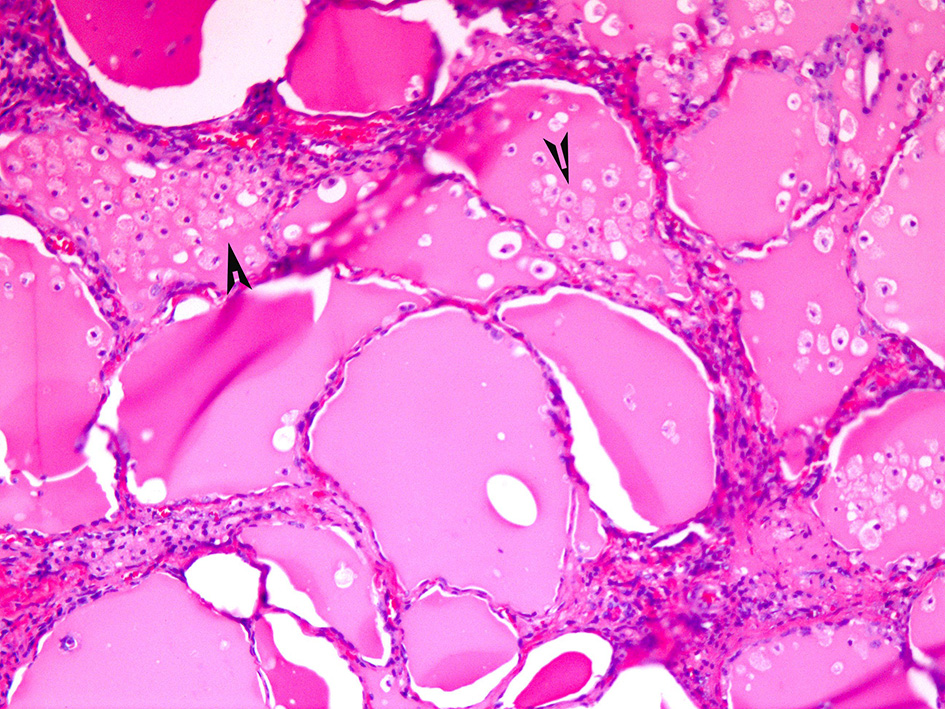

If the gland is already pathologically abnormal (nodular thyroid goiter, Graves' disease), the pathology of the resected gland shows follicular disruption with histiocytes infiltrating the follicular epithelium and colloid (Figures 5, 6). Rarely, inflammatory cells are noted within the thyroid parenchyma (Type I). On the other hand if the thyroid is histologically normal (Type II), the pathologic lesions show much milder follicular damage (73–75). These changes are similar to those seen in amiodarone induced pulmonary and liver toxicity (76, 77). Ultrastructural studies of both lung and thyroid tissues have shown lysosomal and mitochondrial inclusions in follicular cells consistent with follicle cell destruction (77). However, this simple explanation is not the only reason for the thyroid dysfunction. For example, co-cultures of amiodarone with human thyrocytes have shown the production of interleukin 6 and the drug also decreases the sodium-iodide symporter mRNA in the follicular cells (78).

Figure 5. Amiodarone associated follicular cell damage. Low and high power showing large thyroid follicles filled with colloid and numerous histiocytes (arrow heads, 3A,B).

Figure 6. Same as Figure 5.